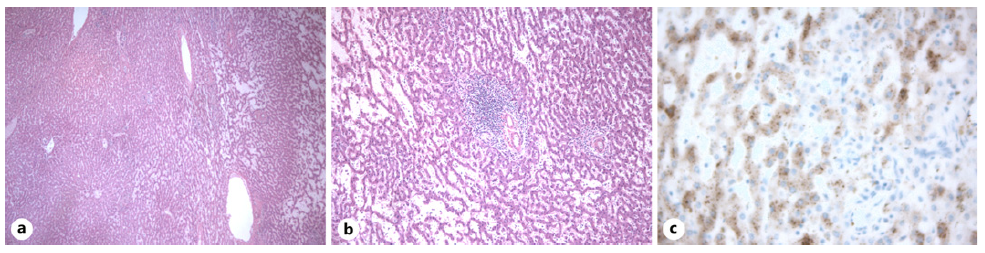

A robot-assisted laparoscopic extended right hepatectomy was performed with no complications. Histologic examination confirmed the definite diagnosis of an inflammatory HCA (shown in Fig. 4).

Fig. 4 Histologic examination. Low- (a) and high-power views (b) showing hepatocellular proliferation with trabecular growth pattern, sinusoidal dilatation, and inflammatory infiltrates. Immunohistochemistry staining of the tumor was liver fatty acid binding protein (LFABP) normal and heat shock protein 70 (HSP70) negative, excluding HCC. Furthermore, reticulin staining was intact, serum amyloid A (SAA) staining was positive (c), with normal nuclear β-catenin and glutamine synthetase staining, confirming the definite diagnosis of an HCA of inflammatory subtype.